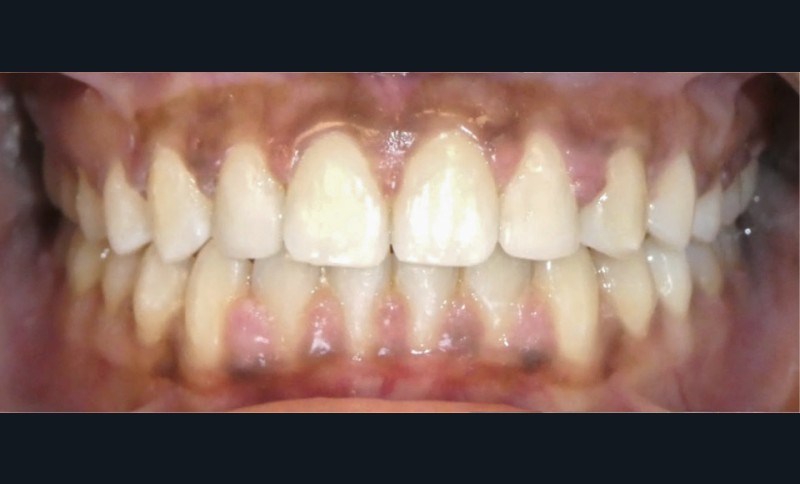

Les objectifs de traitement ont été atteints.

L’esthétique du sourire a été améliorée avec l’augmentation de la visibilité des dents maxillaires, ainsi que la restauration des incisives latérales au composite.

Le profil est plus harmonieux grâce à une diminution de la prochéilie mandibulaire par redressement de l’incisive mandibulaire (fig. 16- 18).

L’auto-transplantation de la 23 sur l’arcade, qui était en position très défavorable, et malgré un apex fermé présente de bons résultats. La radiographie rétro-alvéolaire (fig. 19) montre une intégrité de l’état radiculaire de la dent auto-transplantée. Un suivi régulier reste cependant nécessaire.